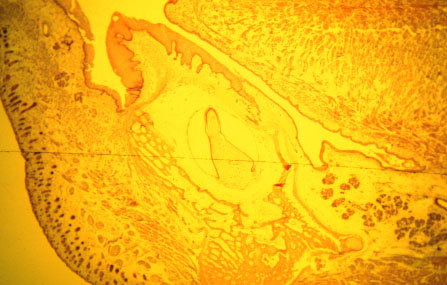

K-slide 14: Identify the lip, tongue, plica sublingualis, sublingual salivary gland, Wharton's duct, developing mandibular bone, remnant of Meckel's cartilage and the tooth primordium.